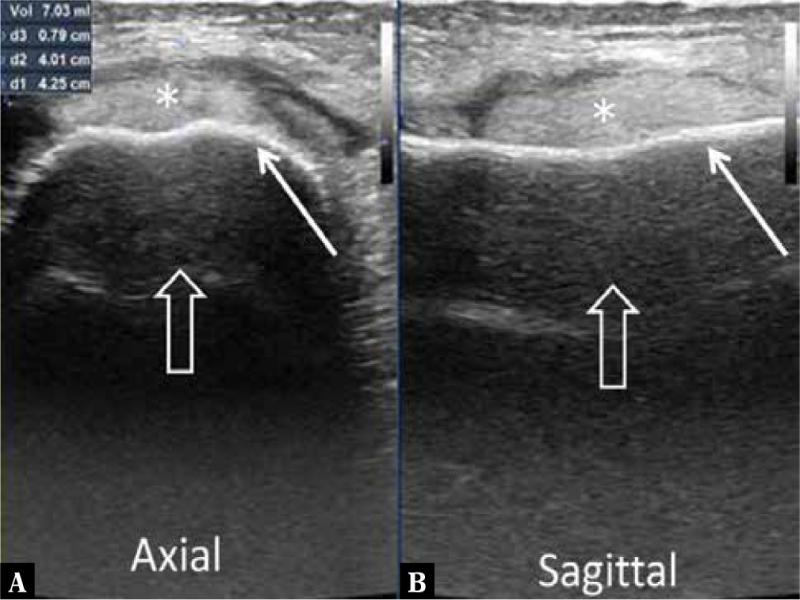

Fig. 2.

| Deep soft tissue fluid collection around the bone | 5 | 100 |

| Periosteal thickening or elevation with subperiosteal fluid collection | 4 | 80 |